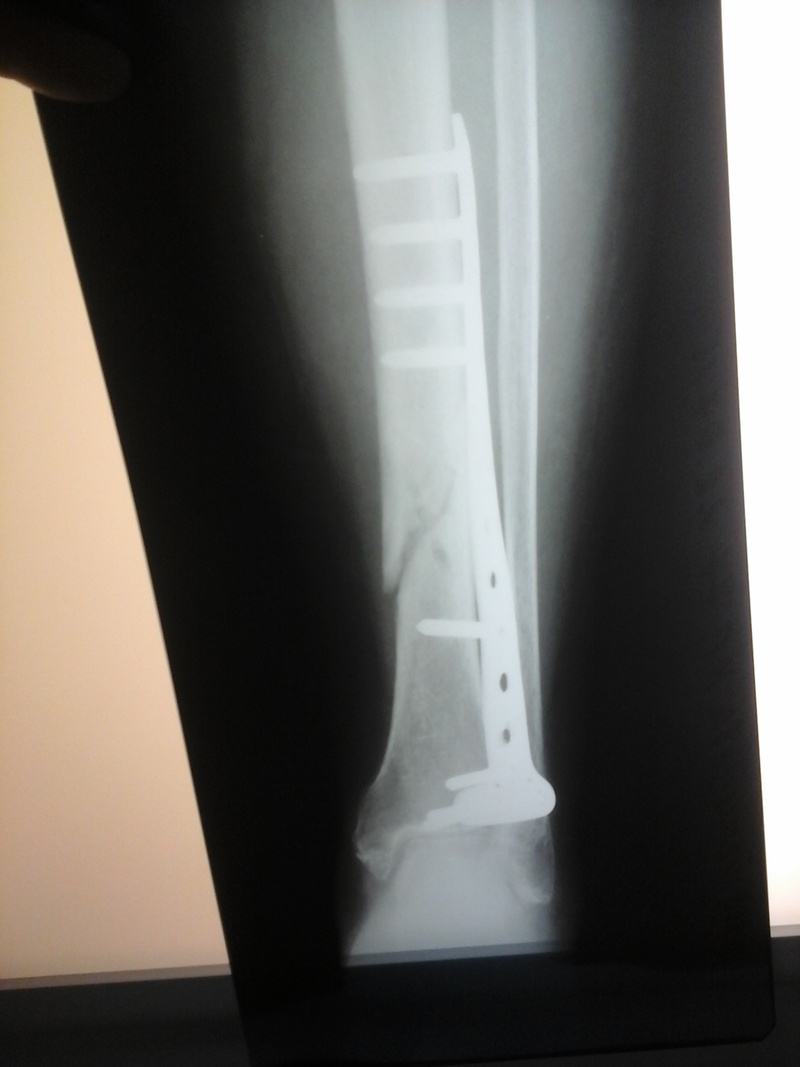

• Весной (2,5 месяца назад) бабуля сломала ногу. Ее положили в городскую клиническую больницу №2 на Ползунова 21. Требовалась операция и врач сказал купить якобы специально изготовленную пластину за 50т.р. что мы и сделали в кратчайшие сроки. Операцию сделали, ногу загипсовали и оставалось только ждать. Ждать сказали не меньше двух с половиной месяцев. Бабуля где на коляске, где на костылях, нога подживала, опухоль сошла, думали все идет как положено, но сегодня ей сделали снимок и мы просто выпали. Кость при операции не совместили, естественно ничего не срастается и не срастется (напомню прошло 2,5 месяца). Нужен грамотный врач для консультации и дальнейшего лечения, посоветуйте к кому обратиться?

• Снимок сделан сегодня

Я тоже не врач, но то что я вижу на снимке говорит мне о том что кость зафиксировали не в нужном положении и сейчас скорее всего пустота заполнится хрящевой тканью которая не сможет нести вес человека.